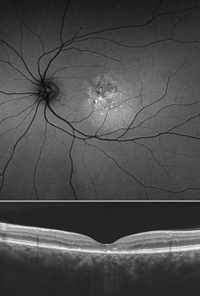

Como ya se ha mencionado, existen varios patrones de hipoautofluorescencia que denotan el daño del EPR en los casos de CSC crónica. Aunque es una enfermedad heterogénea y existe gran variedad de fenotipos clínicos, se ha propuesto una clasificación que divide los casos en tres grupos: hipoautofluorescencia granular, hipoautofluorescencia confluente y tractos descendentes hipoautofluorescentes

8 (

Figura 9). Como parece lógico, los estudios de correlación entre autofluorescencia y OCT demuestran que las áreas de hipoautofluorescencia se corresponden con zonas de atrofia del EPR y de la retina externa en la OCT

6 (

Figura 10).

Figura 9. Patrones típicos de hipoautofluorescencia en la coriorretinopatía serosa central crónica. A) Patrón hipoautofluorescente moteado con alguna placa confluente de hipoautofluorescencia central. B) Placas de hipoautofluorescencia central, que traducen atrofia grave del EPR. C) Tractos descendentes hipoautofluorescentes. Estos tractos típicamente descienden desde la papila (como en la imagen), desde la mácula o desde ambas.

Figura 10. Correspondencia entre la hipoautofluorescencia moteada central (arriba) y las alteraciones puntuales en la línea de los elipsoides en la tomografía de coherencia óptica (abajo).